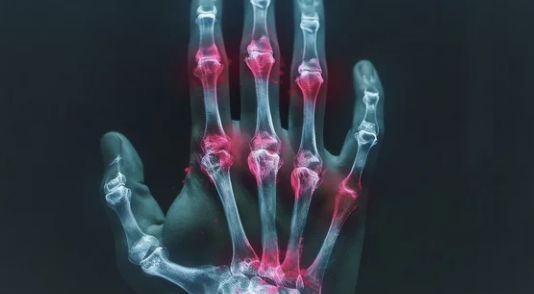

3-2. 진행된 증상

- 관절 부위가 붓고 열감이 느껴진다.

- 관절이 변형되고, 움직임이 제한된다.

Tip: 증상이 나타나면 병원에서 조기 진단을 받는 것이 중요합니다.